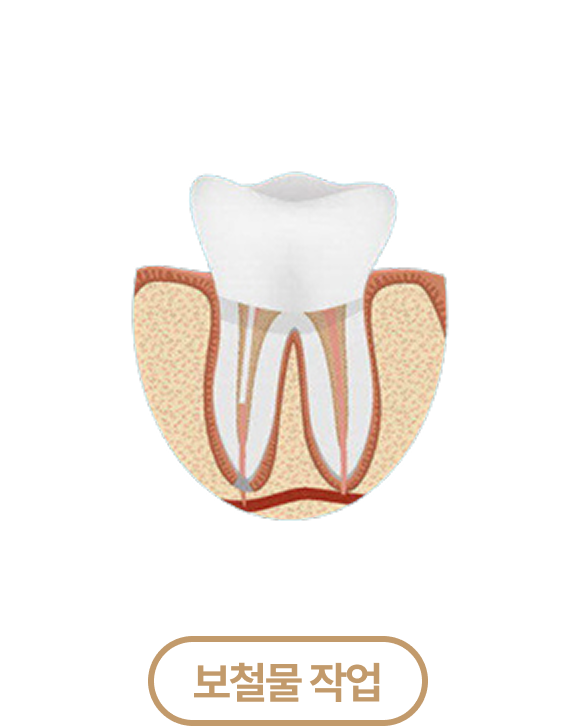

신경치료 치료과정

신경치료 PROCESS

충전 후 치아에 맞는

보철물을 씌워 보호